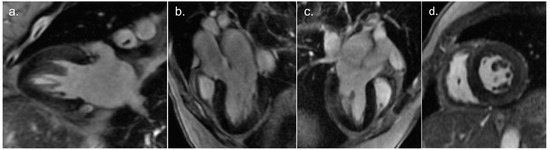

Cardiac magnetic resonance imaging (Videos S3–S6) was performed 10 days after admission, showing preserved LV function (ejection fraction 61%) with lateral wall hypokinesis and mild RV dilatation, with preserved RV function without wall motion abnormalities. Intramural and subepicardial LGE in the basal to mid segments of the inferolateral wall was noted (Figure 3). Native T1 mapping levels were slightly elevated in the myocardial region with LGE. T2 mapping levels were normal.

Figure 3.

Contrast-enhanced magnetic resonance imaging revealing intramural and subepicardial late gadolinium enhancement in the basal to mid segments of inferolateral wall. Two-chamber view (a), three-chamber view (b), modified three-chamber view (c), and mid-ventricular short axis view (d).